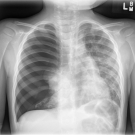

A 3-year-old boy with no medical history presented to the emergency department for worsening cough, decreased appetite, tachypnea, and chest pain for 2 nights.